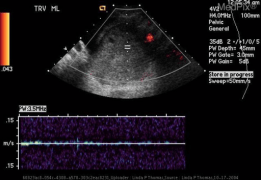

Ovarian Torsion

- Doppler findings:

- Decreased/absent venous or arterial flow

- Absent/reversed diastolic flow

- Can have normal flow (from dual supply from uterine and ovarian arteries)

Large midline ovary with multiple peripherally located follicular cysts (torsion) Absent color doppler and venous and arterial waveforms (torsion)

Absent color doppler and venous and arterial waveforms (torsion)

- Presence of doppler flow cannot rule out ovarian torsion